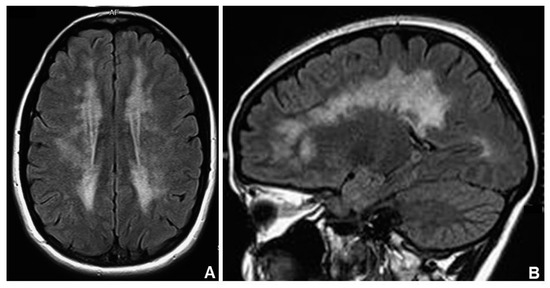

- Scarpelli, M.; Ricciardi, G.G.; Beltramello, A.; Zocca, I.; Calabria, F.; Russignan, A.; Zappini, F.; Cotelli, M.M.; Padovani, A.; Tomelleri, G.; et al. The role of brain MRI in mitochondrial neurogastrointestinal encephalomyopathy. Neuroradiol. J. 2013, 26, 520–530. [Google Scholar] [CrossRef] [PubMed]